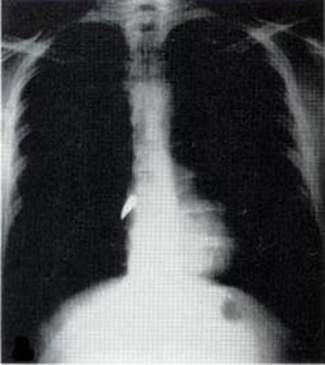

تم اكتشاف الأشعة السينية، وهي نوع من الإشعاع الكهرومغناطيسي، في عام 1895 من قبل فيلهيلم رونتجين، الحائز على جائزة نوبل، وكما وصفتُ في كتابي "الوهج الغريب: قصة الإشعاع"، فقد بدأ الأطباء استخدام الأشعة السينية بعد اكتشافها مباشرة، بتصوير عظام المرضى وإيجاد الأجسام الغريبة، كطلقات الرصاص.

ولكن في بداية الحرب، كان وجود آلات الأشعة السينية مقتصراً على مستشفيات المدن، بعيداً عن ساحات القتال، حيث تتم معالجة القوات المصابة فيها. وكان حل كوري هو ابتكار أول "سيارة إشعاعية" - وهي مركبة تحتوي على جهاز أشعة سينية ومعدات غرفة مظلمة لتظهير الصور- والتي يمكن توجيهها إلى ساحة المعركة حيث يمكن لجراحي الجيش استخدام الأشعة السينية لتوجيه عملياتهم.